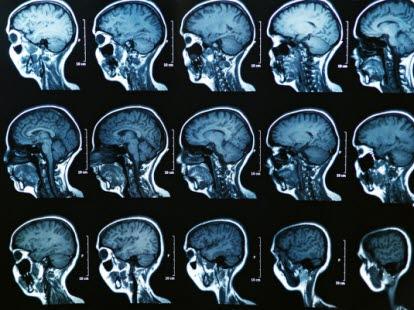

Strålebehandling mot hode og hals

Strålebehandling har en sentral plass i kreftbehandlingen av svulster i hode og hals.

Hode og hals inneholder mange ulike organer. Virkninger og bivirkninger vil variere med hvilket område som behandles. Behandling mot hjernen gir for eksempel andre virkninger enn de du får ved behandling mot stemmebåndene. Følgende er en generell orientering. Du vil få mer konkret informasjon om ditt behandlingsopplegg fra legen, stråleterapeuten eller sykepleieren.